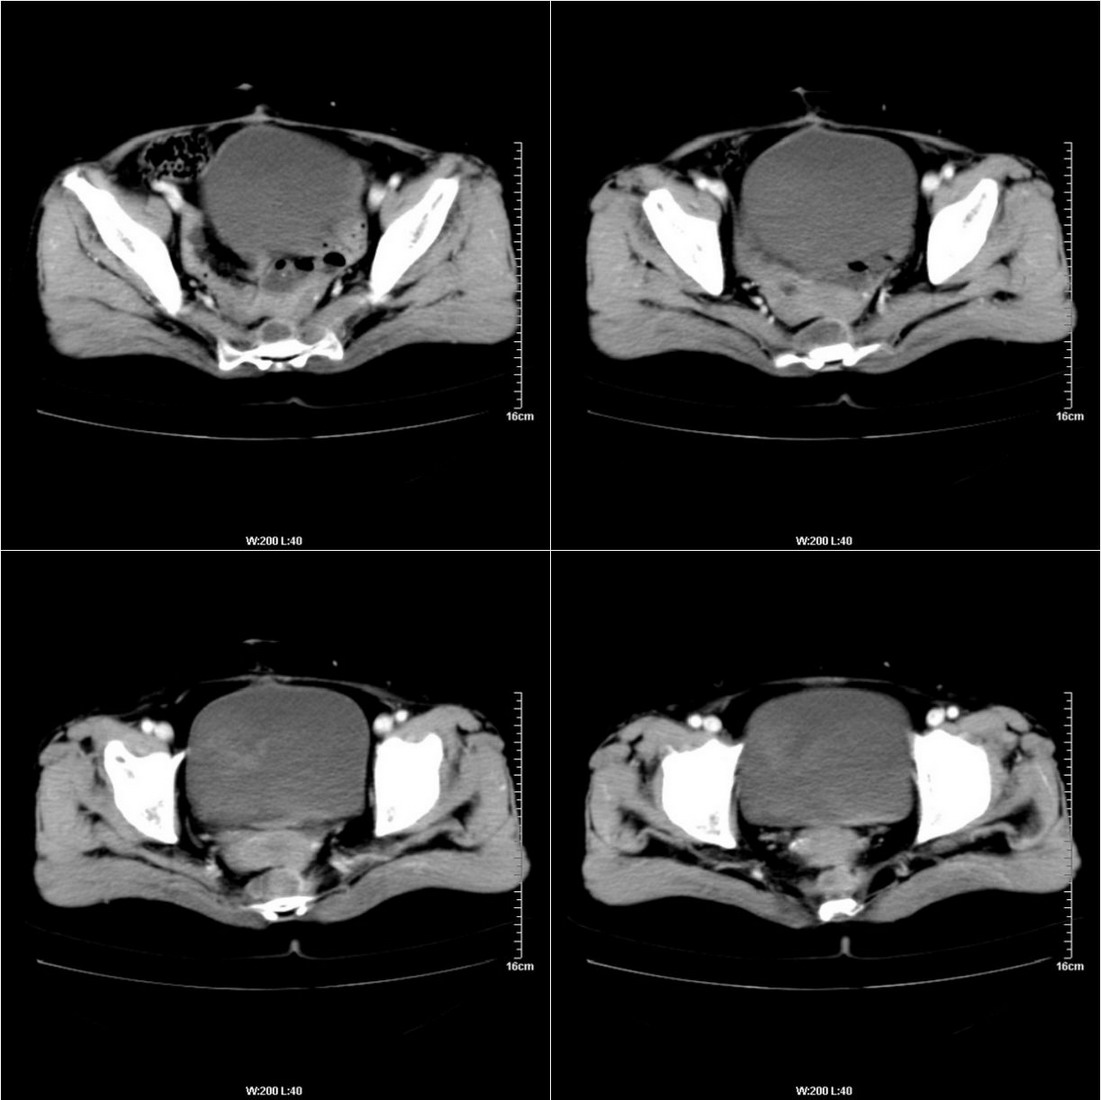

不知道病人的直肠癌手术方式如何,直肠已经全部切除,乙状结肠造瘘于左下腹,肛门应该也没有保留吧?如此,应该是复发了:

病变于肛尾韧带、右侧坐骨肛门窝内并顺右侧肛提肌向右侧闭孔内肌蔓延,骶前软组织内也形成了肿块,麻烦啊!

典型直肠癌术后骶骨前转移复发.

考虑直肠癌术后复发并侵犯周围组织。

考虑直肠癌术后复发并侵犯周围组织

直肠癌术后人工肛门,骶前及术区结节及囊状影,强化不明显,考虑术后瘢痕及粘连包裹可能大,转移不除外。

直肠癌术后骶骨前转移或复发